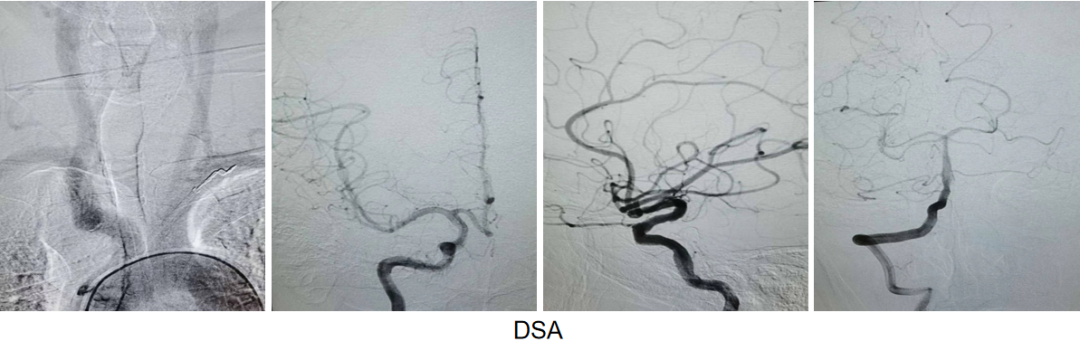

治疗中影像:

导引导管到位,微导丝导引微导管通过病变

球囊通过病变

球囊扩张过程

扩张后造影